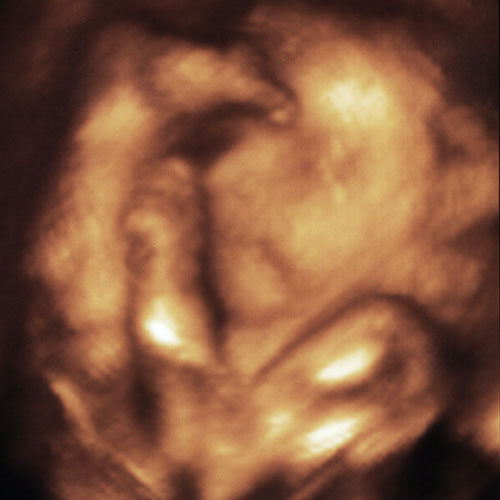

3D Ultrasound of Max at 30 Weeks

3D ultrasound of Max at thirty weeks. Click image to close window.